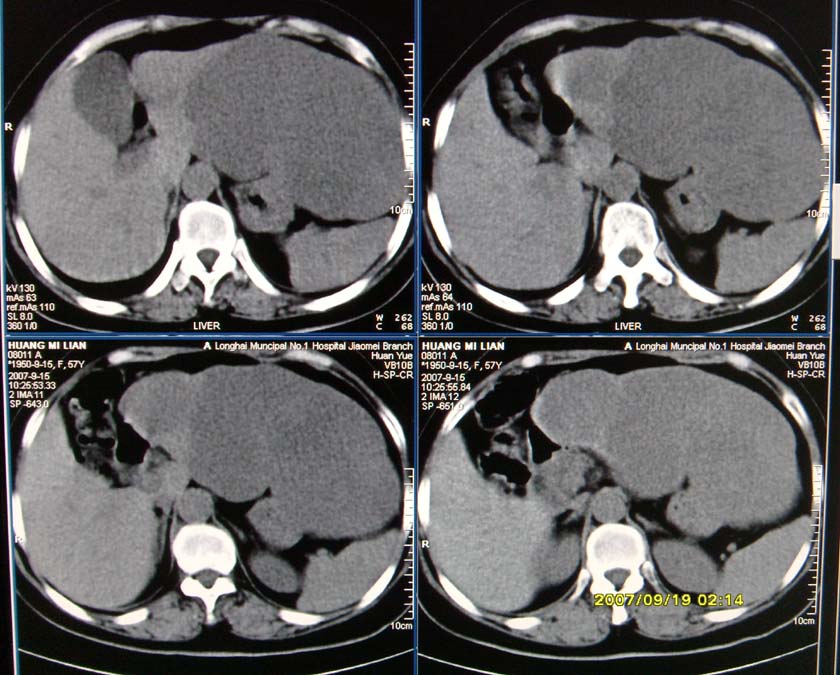

以下是引用逸风在2007-9-19 20:11:00的发言:[br]定位在肝左叶应该没有问题![br]ct显示肝左叶巨大低密度病灶,ct值30hu,密度欠均匀,里面似可见更低密度区;肝门及腹膜后未见明确肿大淋巴结.其与胃之间脂肪间隙存在;彩超提示病灶多发.[br]我个人觉得首先应该增强扫描,从平扫所见结合超声,首先应该考虑血管瘤.

以下是引用davisxuyong在2007-9-19 16:29:00的发言:[br]肝左叶大片状低密度灶,肝癌待排,建议增强。